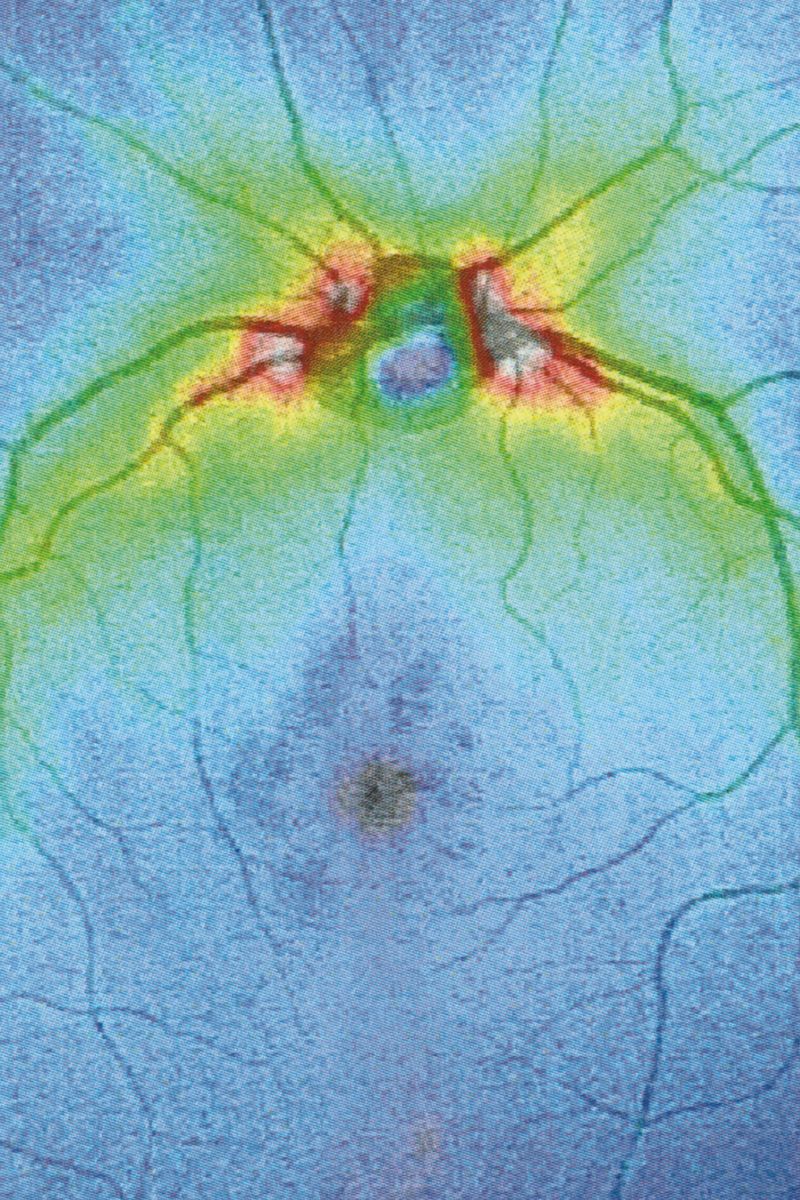

Following a terrifying experience with a too high dose of LSD when I was 16, something has changed in the way I observe visible reality. A hypertrophic screen materialized between me and the world, a scar of opacity. The fear of hallucination teaches a new language, so that every meaning remains trapped in a net and only the signifier filters through its meshes. No shadow, only empty light. Anguish arrests every retinal projection on that screen. Every perception is immobilized to be inspected for a hallucinatory return, it is reified, detached from its real referent, reduced to representation, incapable of referring to something outside of it. And behind (or in front) of it, the eyes have stolen consistency from reality. The body only appears occasionally, at the edges of the mind, when we engage in apperception. And yet I feel the tinkling of a gear that draws my attention inside my eye. I reflect on myself, I look back and from the inside. Once vision is situated in the empirical immediacy of the body, it belongs to time, to flow, to the end.

Collirio (Eye wash) is the attempt to demonstrate the non-absoluteness of visual experience, its nature as a situated, and yet, ambiguous act. It is the path that has allowed me to understand how my fears do not have roots in an unknowable place. The eye is not an unfathomable globe.

When we learn to speak, we are immersed in systems of discourse that pre-exist us and will survive us. So it is with seeing. Between us who observe and the world, there is inserted the set of discourses that constitute visuality and that make it different from vision. Between the retina and the world, a screen of signs is inserted, a screen composed of all the multiple discourses on vision constructed in the arena of collectivity. This screen casts a shadow, Jacques Lacan calls it “scotoma”, “a stain”. Because when we look through the screen, what we see is trapped in a net and can only project towards us the shadow itself of its signifier, its meaning. In the visual field, something cuts, cuts through, parallel to the pupil. It is the fabric of practices, habits, languages, all linked to the reality of representations, with which the meaning of what we see is casted as a shadow.

Collirio is an exercise in comparison. On the one hand, there is the cut left from my lisergic experience, on the other the one described by Lacan, analogue and yet still of opposite function.

The project navigates between these two cuts, attempting to reconnect vision and visuality on a common ground. It seeks to link a personal condition to the more collective one of the gaze, of the images that constitute its archaeology, of abstraction, of the delocalization of the point of view and of the fragmentation of its experience. The acrid smell of vinegar syndrome fills the boxes of reels and rolls. Lucanae are like tired arms, at the end of which is a hand whose grip on meaning has loosened. We are no longer able to grasp it firmly with the same strength. The emulsion begins to separate from its support. The reality of images is no longer able to embody its indexical value as a trace with the same efficacy. Thus, the truth of meaning stops before the surface, unable to emerge. It lingers behind the fiber of a paper sheet, behind the light of a black screen, between the zeroes and the ones of a circuit.